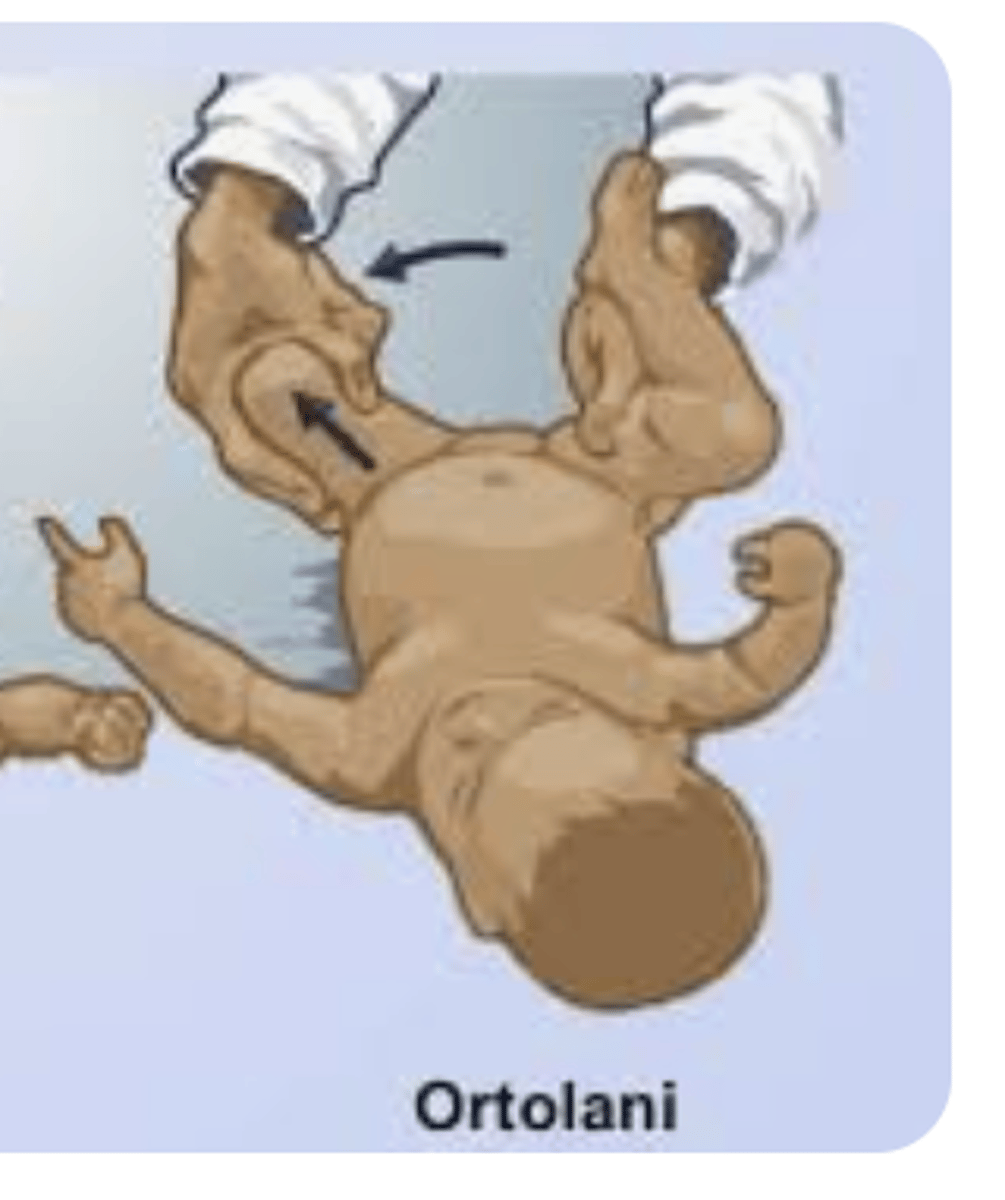

Ortolani's Test

Flex Hips/Knees + Abduct

(+) = relocation